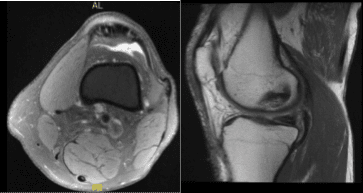

The patient got a cortisone injection, which helped him transiently but the pain came back. There is mild mucoid degeneration of the anterior cruciate ligament. There is mild proximal medial collateral ligament sprain with associated periligamentous soft tissue edema which extends along the posteromedial capsule.

There is mild popliteus insertional tendinosis. We discussed the treatment options and the patient opted for surgical management, including risks and complications of surgery and need for cortisone injection and PT as well.